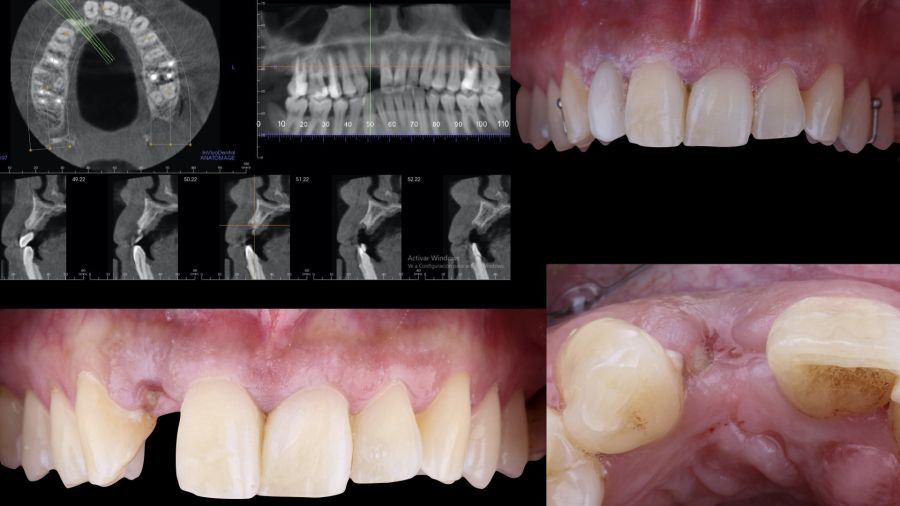

1.1 Diagnosis and Treatment Plan

A 29-year-old female patient presented to our dental clinic following trauma to the right maxillary lateral incisor (1.2). The trauma resulted in a fracture of the entire anatomical crown; consequently, only a root remnant in a subgingival position remained. The root remnant was diagnosed as non-restorable, and the available therapeutic options were thoroughly discussed with the patient. It was decided to replace tooth 1.2 with a dental implant, and the following treatment plan and clinical sequence were established: Phase I: extraction of the root remnant 1.2 and reconstruction of the alveolar process using a minimally invasive alveolar preservation procedure.

Immediate provisional restoration using a removable partial acrylic prosthesis. Phase II: guided placement of an implant and augmentation of mucosal thickness with a connective tissue graft. Phase III: shaping and modelling

* Phase II: healing proceeded without complications. After 5 months from the alveolar preservation surgery, guided implant surgery was planned at position 1.2 (Figure 2). For this purpose, a DICOM file from cone beam computed tomography (CBCT) and an STL file obtained from scanning with an intraoral optical scanner were used. Using this information, a dental support surgical guide was fabricated (Figure 3). The surgical guide was anchored onto the teeth and guided the preparation of the implant bed and the placement of the implant. The guided surgery technique consisted of flap surgery, preparing and inserting the implant (3.5 x 11.5 mm) according to the standardised Nobel Active® guided surgery protocol (Nobel Biocare AB, Gothenburg, Sweden). Once implant 1.2 was placed,a gingival graft composed of epithelium and connective tissue from the palatal masticatory mucosa was obtained. Subsequently, the superficial epithelial layer of this graft was deepithelialised extraorally using a 15C scalpel blade in order to obtain a connective tissue graft from the underlying layer18.